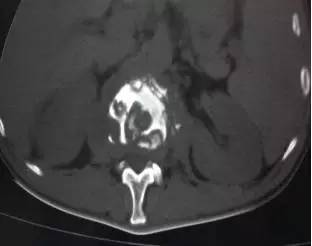

本例腰椎结核位于腰1-2椎体,相应椎间隙变窄,椎旁脓肿形成。

本病发病率高的原因:其一,脊柱为躯干的支柱,而腰椎负荷大,在日常生活中发生劳损的机会多;其二,结核多侵犯松质骨,腰椎结核多发于成年人。